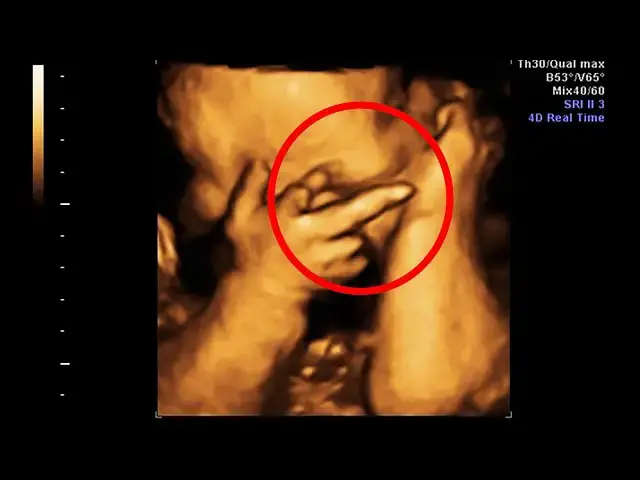

Mom Thinks She’s Pregnant With Twins, Doctor Freezes When He Sees Her Ultrasound

Mom Thinks She’s Pregnant With Twins, Doctor Freezes When He Sees Her Ultrasound.

At first, everything with the ultrasound seemed to go well. Then the doctor noticed something that made the hair on his arms stand up. He could not believe what he saw on the monitor. In an instant, the couple’s pregnancy took a dramatic turn. Read on to discover the story of the Perkins and their astonishing journey…